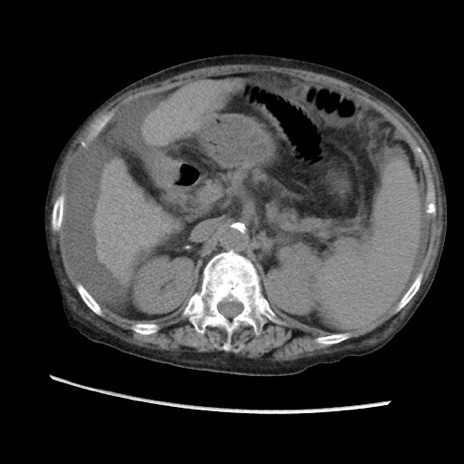

症例31(横断像)

【症例】80歳代 女性

【主訴】腹部膨満感

【現病歴】他院にて肝硬変にてフォロー中。1週間前から便秘、腹部膨満感、臍部腫瘤あり受診となる。

【既往歴】肝硬変

【身体所見】腹部膨隆あり、皮膚変化なし、疼痛なし。

【データ】WBC 4600、CRP 0.25